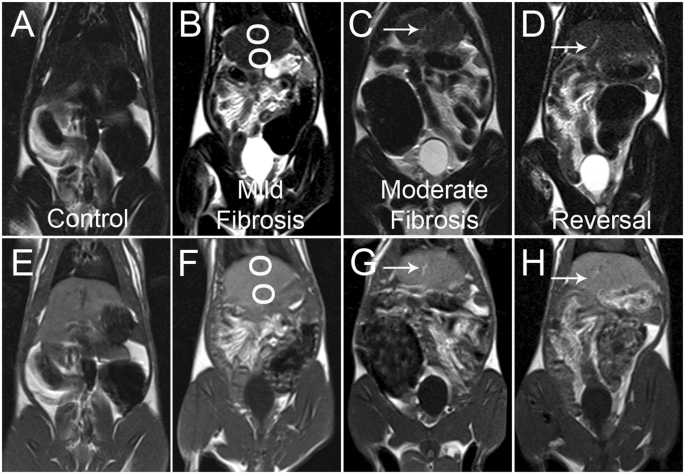

T1 and T2 weighted liver MR images of control, mild fibrosis, moderate fibrosis and reversal group of animals are shown in Fig.Ā 7. T1 and T2 weighted imaging are standard protocols adopted for imaging in MRI. Information on the spin-lattice relaxation of the hydrogen protons of the tissue are reconstructed to get the T1 weighted images in MRI, whereas spin-spin relaxation, gives the T2 weighted images. In T1 weighted MR images, the mild fibrosis as well as the normal liver looks similar, without any major differences. Moderately fibrosed liver exhibits intermittent patches of hyper intensive areas51. But there is no remarkable visual delineation between the normal control and the mild fibrosis. T2 weighted image of mild fibrosis shows a lacelike pattern which is absent in the control. Characteristic morphological alterations such as surface nodularity, widening of fissures and relative enlargement of the lobes can be visualized in the MR image of the moderately fibrosed liver. Residual nodularity can be seen in the reversal group (Fig.Ā 7D). The actual site of mild fibrosis/moderate fibrosis and the exact margins cannot be precisely distinguished from the MR image.

(AāD) T2 weighted and (EāH) T1 weighted MR images of control (A and E), mild fibrosis (B and F), moderate fibrosisĀ (C and G) and reversal (D and H) animals. Circles mark the fibrosed areas while the arrows mark the compartmentalisation of the liver in the moderate fibrosis. Lace like structure is visible throughout the organ in T2 weighted image of fibrosis.

The fibrosed areas are observed as low-signal-intensity reticulations on T1 weighted images and high-signal-intensity reticulations on T2 weighted images in the moderate fibrosis. These are indications of advanced fibrosis which is not visible in the images of control and mild fibrosis. The overall pixel intensity change is evaluated from the images and is shown in Fig.Ā 8. As T1 weighted images provide an overall enhancement of pixel intensity, low intensity reticulations are not clearly visible whereas the visibility is better in the case of T2 weighted image. The results indicate that routine MR imaging is insufficient to provide biochemical details as well as the changes corresponding to various stages of liver fibrosis. It is reported that contrast enhanced MR imaging and advanced MRI techniques like MR spectroscopy and diffusion weighted imaging are preferred over conventional imaging for early diagnosis of liver fibrosis33,34,52. When externally administered contrast agents are required in the first case, advanced MRI sequences for measuring the apparent diffusion coefficient of water has to be run in the second case. In addition to the risk of injecting highly toxic gadolinium based contrast agents, these techniques involves high cost and extra time for running the additional MRI sequences, making it unreachable for common man.